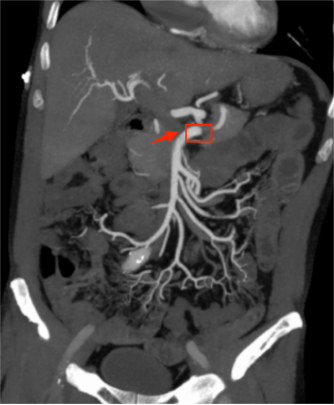

术后腹部增强CT:原肠系膜上动脉近端血栓消失,血管再通

术后第3天复查腹部CTA示:原肠系膜上动脉近段、右结肠动脉近端、小肠动脉近端充盈缺损已消失,各分支显影好。